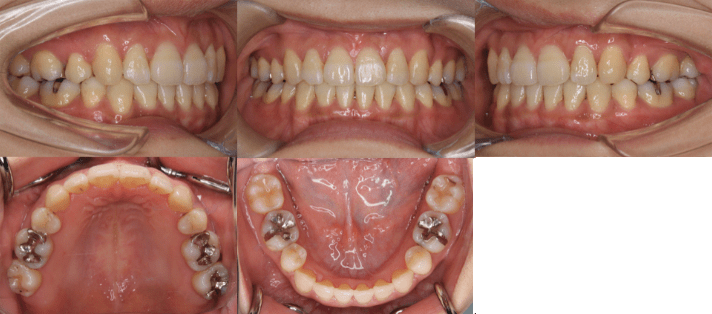

<治療後>

| 初診時年齢 | 25歳7ヶ月 |

| 主訴 | 前歯のガタガタ |

| 診断 | 交叉咬合を伴う叢生症例 |

| 治療内容 | 小臼歯4本を抜歯した後、インビザラインを使用して主訴である叢生の改善を行いました。 |

| 治療期間 | 2年 |

| リスク | 矯正治療による歯の移動に伴う痛み、歯根吸収、虫歯 |

| 費用 | 80万円 |